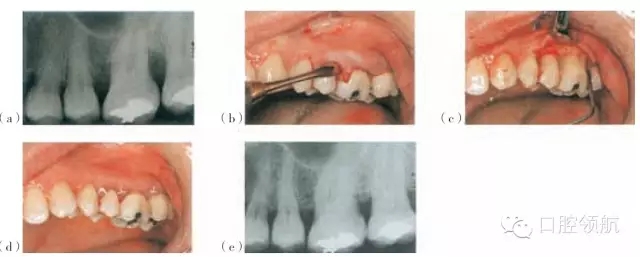

圖26.5 使用Emdogain®和PerioGlas®處理的一個病例。(a)手術位點的術前放射線圖像。(b)頰側(cè)瓣的影像。(c)使用EDTA調(diào)節(jié)器后應用Emdogain®。(d)瓣的復位與縫合。(e)術后18個月的放射線圖像

Straumann®, Emdogain也可以被用在骨移植材料的結(jié)合處,例如作為骨沉積的支架(圖26.5)的Bio-Oss®(GeistlichPharma AG),PerioGlas®或者StraumannBoneCeramic 400-700®。Emdogain®還可以與GTR技術聯(lián)合應用。